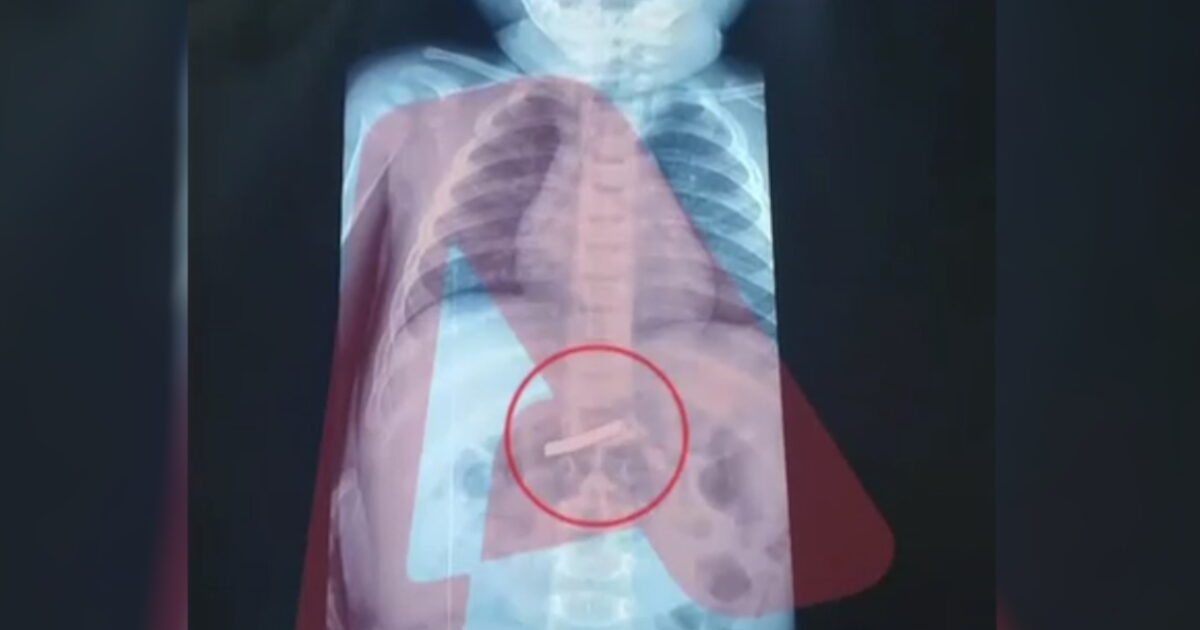

Ένας 3χρονος μεταφέρθηκε εσπευσμένα στο νοσοκομείο, το οποίο κατάπιε ένα ξυραφάκι. Το παιδί αφού έφτασε σε Παίδων της Αθήνας, υποβλήθηκε άμεσα σε ακτινογραφία, η οποία έδειξε ότι όντως υπήρχε το αιχμηρό αντικείμενο στο στομάχι του.

Όπως ενημέρωσαν οι γιατροί, τους γονείς του παιδιού, μετά την ακτινογραφία προσδιορίστηκε και το ακριβές σημείο όπου βρέθηκε το ξυραφάκι, ώστε οι χειρουργοί να προχωρήσουν σε επέμβαση αφαίρεσής του με ασφάλεια.